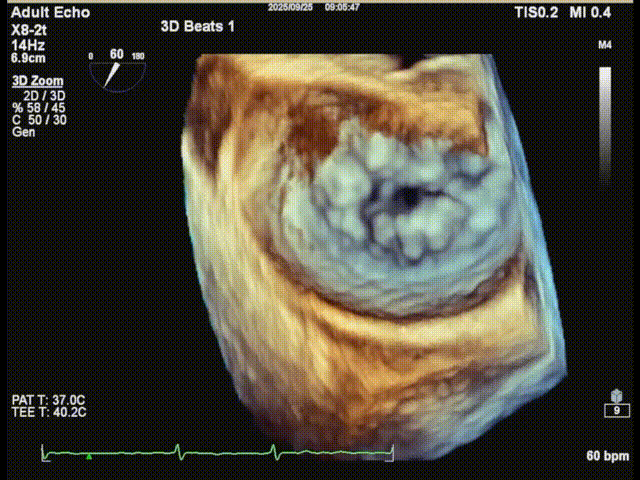

二尖瓣3D

三尖瓣

三尖瓣反流以膈叶脱垂为主,反流主要集中在前叶和膈叶间,从中心区向边缘区的蔓延。后叶又有分了两个叶,分型上属于IIIb型的三尖瓣反流。